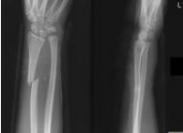

先天性Madelung畸形(馬德隆畸形),是橈骨遠端尺側(cè)及掌側(cè)骨骺發(fā)育障礙引起的先天性遠端橈尺關(guān)節(jié)半脫位畸形。也有人稱其為先天性腕關(guān)節(jié)半脫位,橈骨遠端骨骺發(fā)育缺陷和尺側(cè)部比橈側(cè)部短等。

- 常見癥狀:不明原因尺骨莖突異常突起、腕關(guān)節(jié)向掌側(cè)、橈側(cè)移位、活動受限、前臂旋轉(zhuǎn)功能受限、女性多見